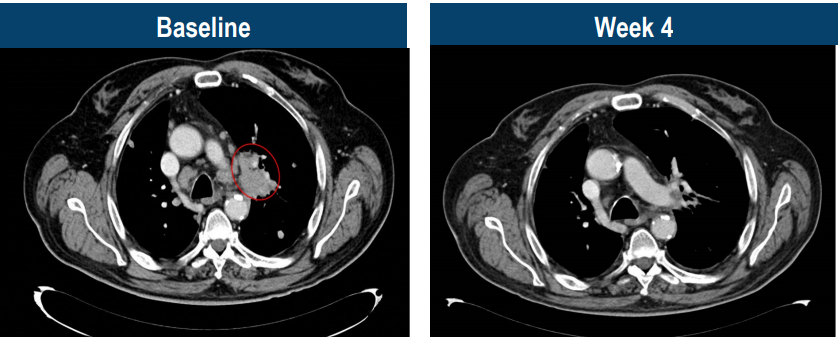

典型病例

这是一名69岁的男患者,被确诊为4期头颈癌,接受了化疗和PD-1治疗后病情仍不断进展,肿瘤转移至肺等多部位。幸运的是,经过检测存在MAGE-A4高表达,当50亿能够精准识别癌细胞的TCR-T大军回输到M先生体内后,仅4周,肿瘤快速消退,达到部分缓解!